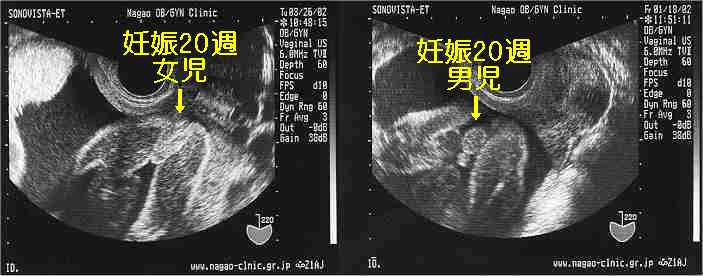

Egg 妊娠中期の超音波画像(女児、男児)

以下は妊娠20週(6ヶ月初め)の経膣超音波画像をご覧頂いています。左が女児、右が男児の外陰部超音波画像で、それぞれ大陰唇、陰嚢陰茎が描出されています。